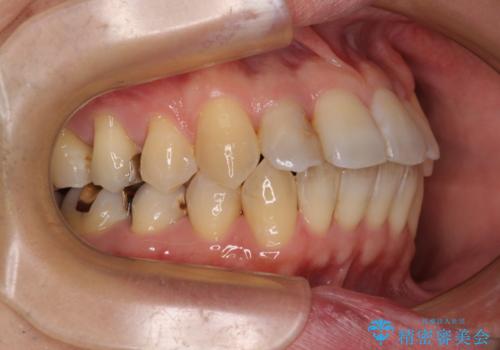

舌の突出癖の影響か、下顎前歯がなかなか整わず、治療期間は予定よりも長期間となりました。

舌突出癖改善のトレーニングの重要性を認識することとなりました。

- 治療中は歯磨きがしにくくなるため、虫歯や歯周病になりやすくなります